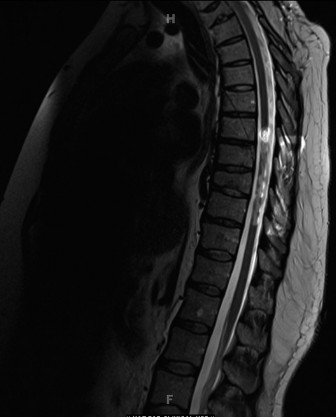

Advanced Imaging and Diagnostics

The initial radiographic evaluation of the swollen thigh will confirm the presence of a femur fracture. However, the diagnostic workup for a non-ambulatory infant with a suspicious fracture must immediately pivot to a systemic evaluation for occult injuries. The historical practice of ordering a "babygram"—a single, large-cassette radiograph encompassing the entire infant—is obsolete, medically unacceptable, and medicolegally indefensible. A babygram suffers from severe parallax distortion, inadequate penetration of thicker body parts, and over-penetration of thinner parts, rendering it useless for detecting subtle, high-specificity fractures.

The Skeletal Survey Protocol

The gold standard diagnostic imaging modality is a formal, high-detail Skeletal Survey, performed according to the rigorous guidelines established by the American College of Radiology (ACR) and the American Academy of Pediatrics (AAP). This survey consists of 21 distinct, tightly collimated radiographic views, including bilateral AP and lateral views of the skull, AP and lateral views of the axial skeleton (cervical, thoracic, and lumbar spine), AP views of the bilateral humeri, forearms, femurs, and lower legs, as well as specific views of the hands, feet, and pelvis.

We are specifically hunting for fractures that carry a high specificity for child abuse. These include the Classic Metaphyseal Lesions (CMLs), posterior rib fractures (caused by the clinician's or abuser's hands squeezing the infant's thorax, levering the ribs over the transverse processes), scapular fractures, spinous process fractures, and sternal fractures. Furthermore, the skeletal survey allows us to identify fractures in various stages of healing. Finding a fresh, acute femur fracture alongside a healing posterior rib fracture with robust callus formation proves that the child has been subjected to multiple traumatic events over time, cementing the diagnosis of NAT.

Advanced Neuroimaging and Laboratory Workup

Given the high correlation between abusive skeletal trauma and abusive head trauma, a non-contrast Computed Tomography (CT) scan of the head is mandatory in infants under 6 months of age presenting with high-suspicion fractures, even if they are neurologically intact. We are screening for subdural hematomas, subarachnoid hemorrhage, and cerebral edema.